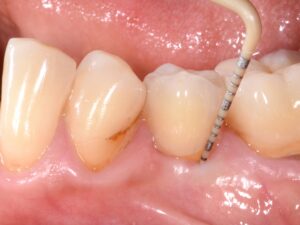

Implant Patent™ chez un patient présentant des facteurs de risque après 4,5 ans : À la différence des implants dentaires classiques, les implants Patent™ ne montrent aucune formation de poche. Leur « bond » stable avec les tissus mous permet de maintenir des profondeurs de sondage limitées à 3 mm au maximum, similaires à celles d’une dent naturelle en parfaite santé. (Copyright Dr Roland Glauser)

Leurs travaux démontrent que les cellules épithéliales adhèrent naturellement à la surface transmuqueuse des implants Patent™, formant dès les premiers jours une barrière de défense dynamique contre la plaque et les bactéries.